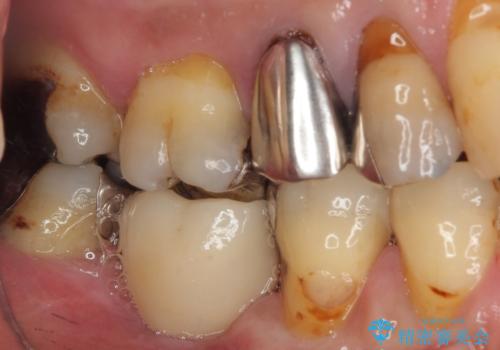

- 奥歯を抜歯してから放置しているとのことで来院された患者様です。

歯が割れて抜歯になってしまったとのことで、咬合力に抵抗できるよう、インプラントによる補綴治療を行うこととしました。

むし歯の放置期間と抜歯してからの放置期間が長く、咬み合わせる上顎の歯がやや伸び出している状態でした。

上顎の部分矯正や対合歯の補綴治療も提案しましたが、今回は欠損部のみの治療を行いました。